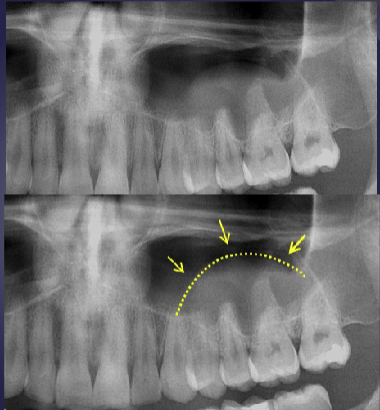

3 radiographic features of mucus retention “pseudocyst”

relative radiopacity on floor of sinus

well-defined, not corticated

dome-shaped